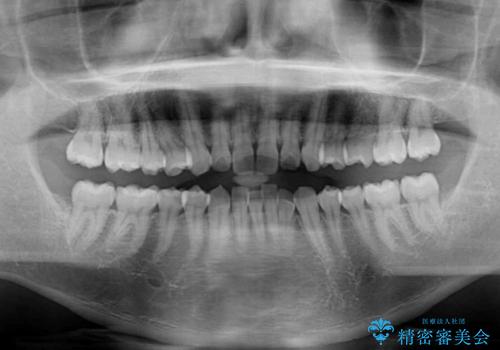

- 上下前歯のデコボコを気にして来院された患者様です。

インビザラインによる上下歯列の側方拡大と後方移動、IPR(歯と歯の間を削る)にるスペースの獲得により歯列を整えることとしました。

左上の小臼歯は捻転が強く、あえて180逆向きの状態で終了させる治療計画としました。